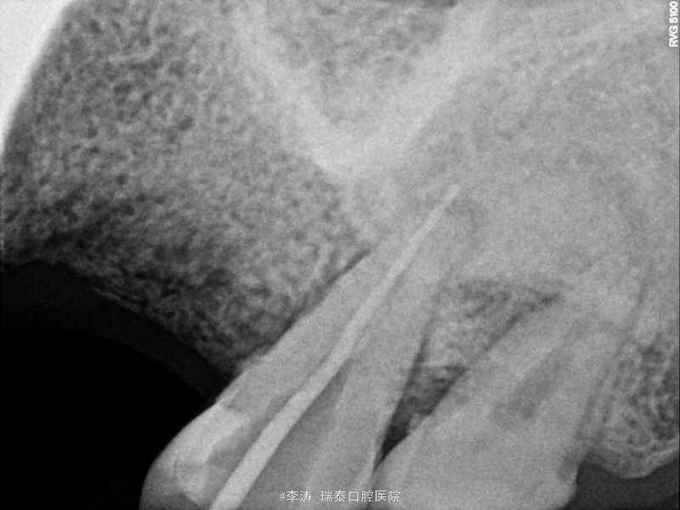

根尖区病变牙的治疗一例

牙骨质瘤 牙骨质瘤

26残冠 25,27根管治疗不到位 27牙根尖区高密度影 所有牙均无临床症状

经多方会诊,确认考虑27牙根尖牙骨质瘤,建议先行根管治疗,然后密切观察 予以拔除26,根管治疗25,27